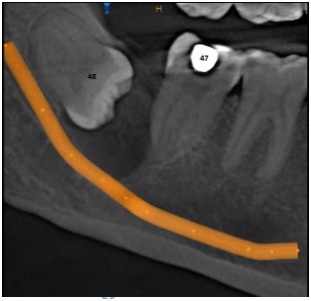

INVESTIGATIONS

Radiovisiography

Laboratories / Facilities